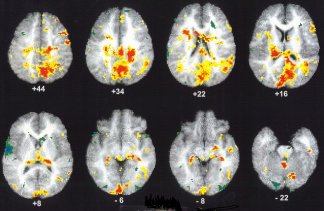

During the experiment, each kid lay inside a special brain-imaging machine. Such a machine takes pictures of the brain and shows which parts of the brain are working at different times.

Murray and his colleagues found that exposure to violent video clips activated the amygdala, a thumbnail-sized area in the brain. The right side was particularly active.

The colored parts of these images—each one a cross section of a brain—show which parts of the brain are active when children view a violent video clip but not when they view a nonviolent clip.

| John Murray, Kansas State University |

The amygdala is best known as the “fight or flight” organ. It senses danger and prepares you to either go to battle or run away. Your breathing slows down. You become hyper-aware of movements in the environment. And blood rushes to your brain’s core, among other effects.